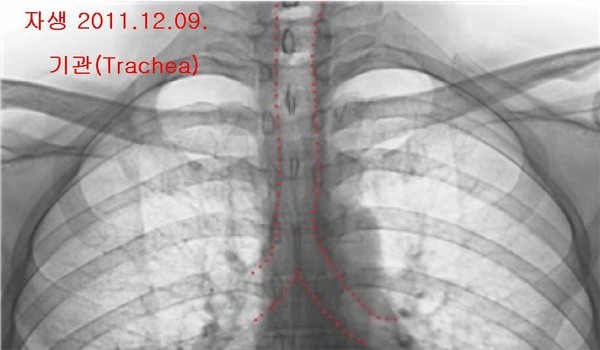

- ▲ 박주신씨 명의 엑스레이(위로부터 공군·자생). 기관의 주행 형태를 볼 수 있다. ⓒ 의료혁신투쟁위원회

특히 남 전 교수는 “피사체의 고개를 돌리거나 꺾는 등 자세를 바꾼 상태에서 촬영을 해도 기관의 모양은 변하지 않았다”며, 촬영방식이나 호흡법, 자세 때문에 기관의 방향이 다르게 보일 수 있다는 주장은 납득하기 어렵다고 설명했다.남 전 교수는 엑스레이를 해부학적 관점에서 분석한 결과, 촬영 당시 호흡상태의 차이에도 불구하고, 흉곽 모양은 크게 차이가 나지 않는다는 점도 확인할 수 있다고 덧붙였다.

감정 대상이 된 주신씨 명의의 엑스레이는 ①자생병원 엑스레이(2011년 12월 9일), ②공군훈련소 엑스레이(2011년 8월 30일), ③주신씨가 영국 출국에 앞서 비자발급을 위해 세브란스병원에서 촬영한 엑스레이(2014년 7월 31일) 등 3장이다.

쟁점②, 증인 “기관의 뻗은 모양, 호흡법 따라 다르게 보일 수 있지만, 이런 견해를 뒷받침할 논문은 없다”종격동 안에 위치한 기관의 주행방향, 즉 뻗은 모습이 엑스레이 촬영순간 호흡상태에 따라 다르게 보일 수 있다는 검찰 감정인들의 견해도 주요 쟁점으로 떠올랐다.

차기환 변호사는 류OO 교수가 1심 재판 감정서에 기재한 내용을 바탕으로, 호흡상태에 따라 기관의 뻗은 모양이 다르게 보일 수 있는지를 캐 물었다.

이를 위해 차 변호사는 사람이 음식물을 먹는 순간 기관의 모습이 어떻게 변하는지를 확인할 수 있는 동영상을 증인과 재판부에 보여주면서, “음식물을 넘기는 상황에서도 기관의 주행방향은 바뀌지 않는다는 사실을 알 수 있다”며, 검찰 측 감정인들이 낸 감정의견의 신뢰도에 의문을 표했다.

류OO 교수는 “호흡 상태에 따라 기관의 모습이 달리 보일 수 있다는 견해를 뒷받침할 만한 텍스트나 논문 등을 제출할 수 있느냐”는 차기환 변호사의 질문에 “없다”고 짧게 답했다.

류OO 교수는, 기관 주행방향이 호흡 상태에 따라 직진 혹은 휘어진 형태로 보일 수 있다는 감정서 기재내용의 작동원리를 설명할 수 있느냐는 질문에 대해서도 “그렇지 않다”고 답했다.

차 변호사는 피고인 측 감정인인 오연상 박사와 김OO 연세대 의대 교수의 감정의견, 남동기 전 아주대 교수의 실험결과를 각각 인용하면서, 호흡 상태나 자세를 달리한다고 해도 기관의 주행방향이 바뀌지는 않는다고 지적했다.

<차> 공군과 비자 엑스레이 피사체의 기관은 안쪽(오른쪽)으로 굽은 형태, 자생 엑스레이 피사체의 기관은 곧은(직진) 형태로 나온다. 그런데 증인은 이런 차이가 나타나는 원인을, 촬영 자세와 호흡의 차이 때문이라고 설명했다.

<증> 촬영 자세나 호흡이 다르면 충분히 저런 변화가 관찰될 수 있을 것으로 생각했다.